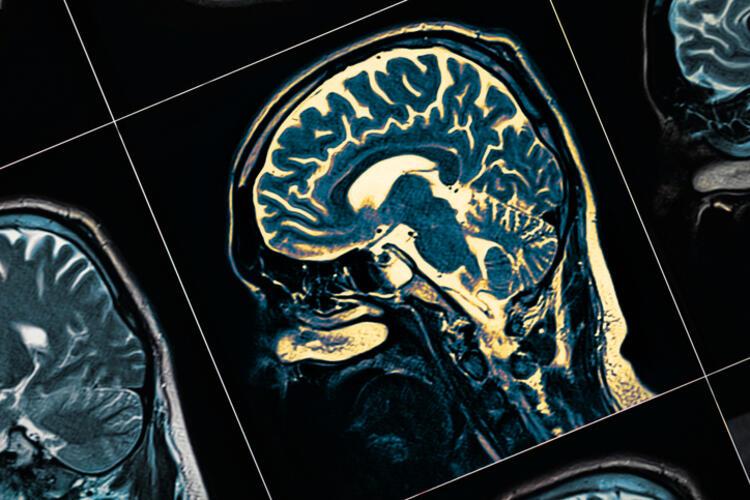

- Adeta büyük bir fabrika gibi çalışan ve vücudumuzdaki tüm fonksiyonları kontrol eden insan beyninin 80 milyardan fazla sinir hücresinden (nöron) oluştuğunu biliyor muydunuz? Ya her bir nöronun diğer nöronlarla iletişim kurmak için milimetreden küçük kablolara benzeyen çok sayıda uzantılarının (aksonlar ve dendritler) olduğunu?